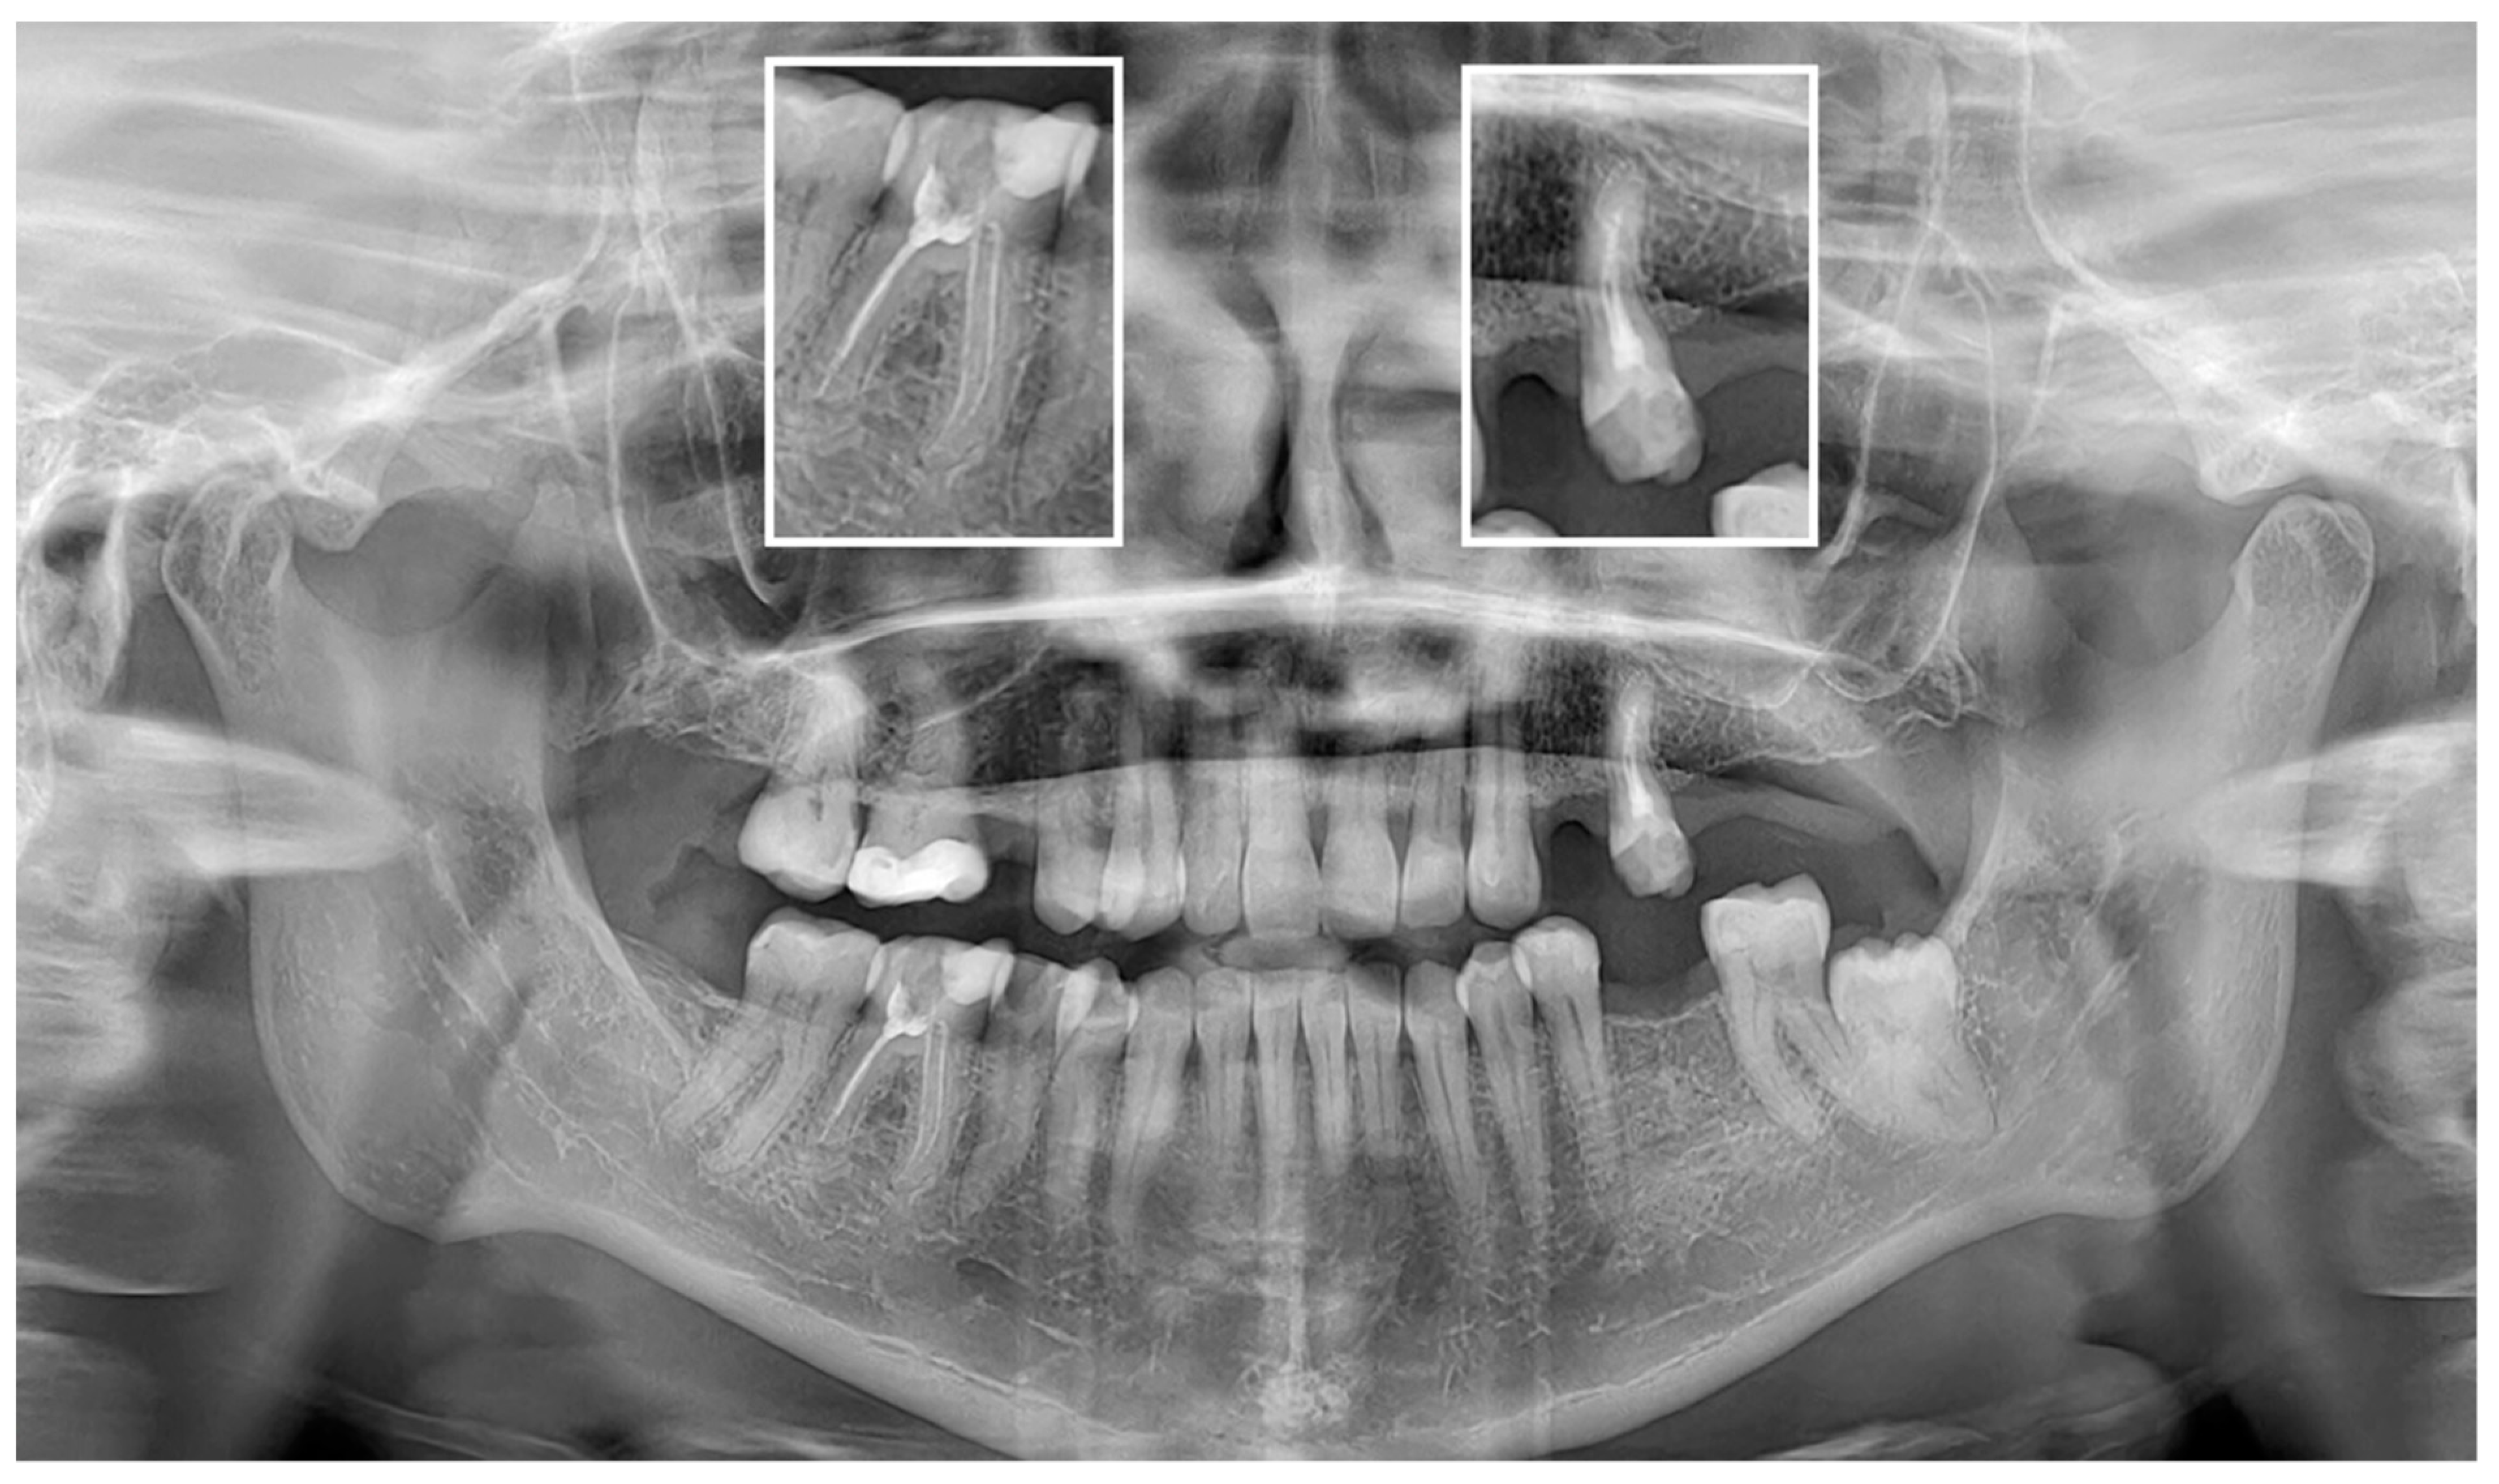

3. Results

3.2. Diagnostic Accuracy Parameters

4. Discussion